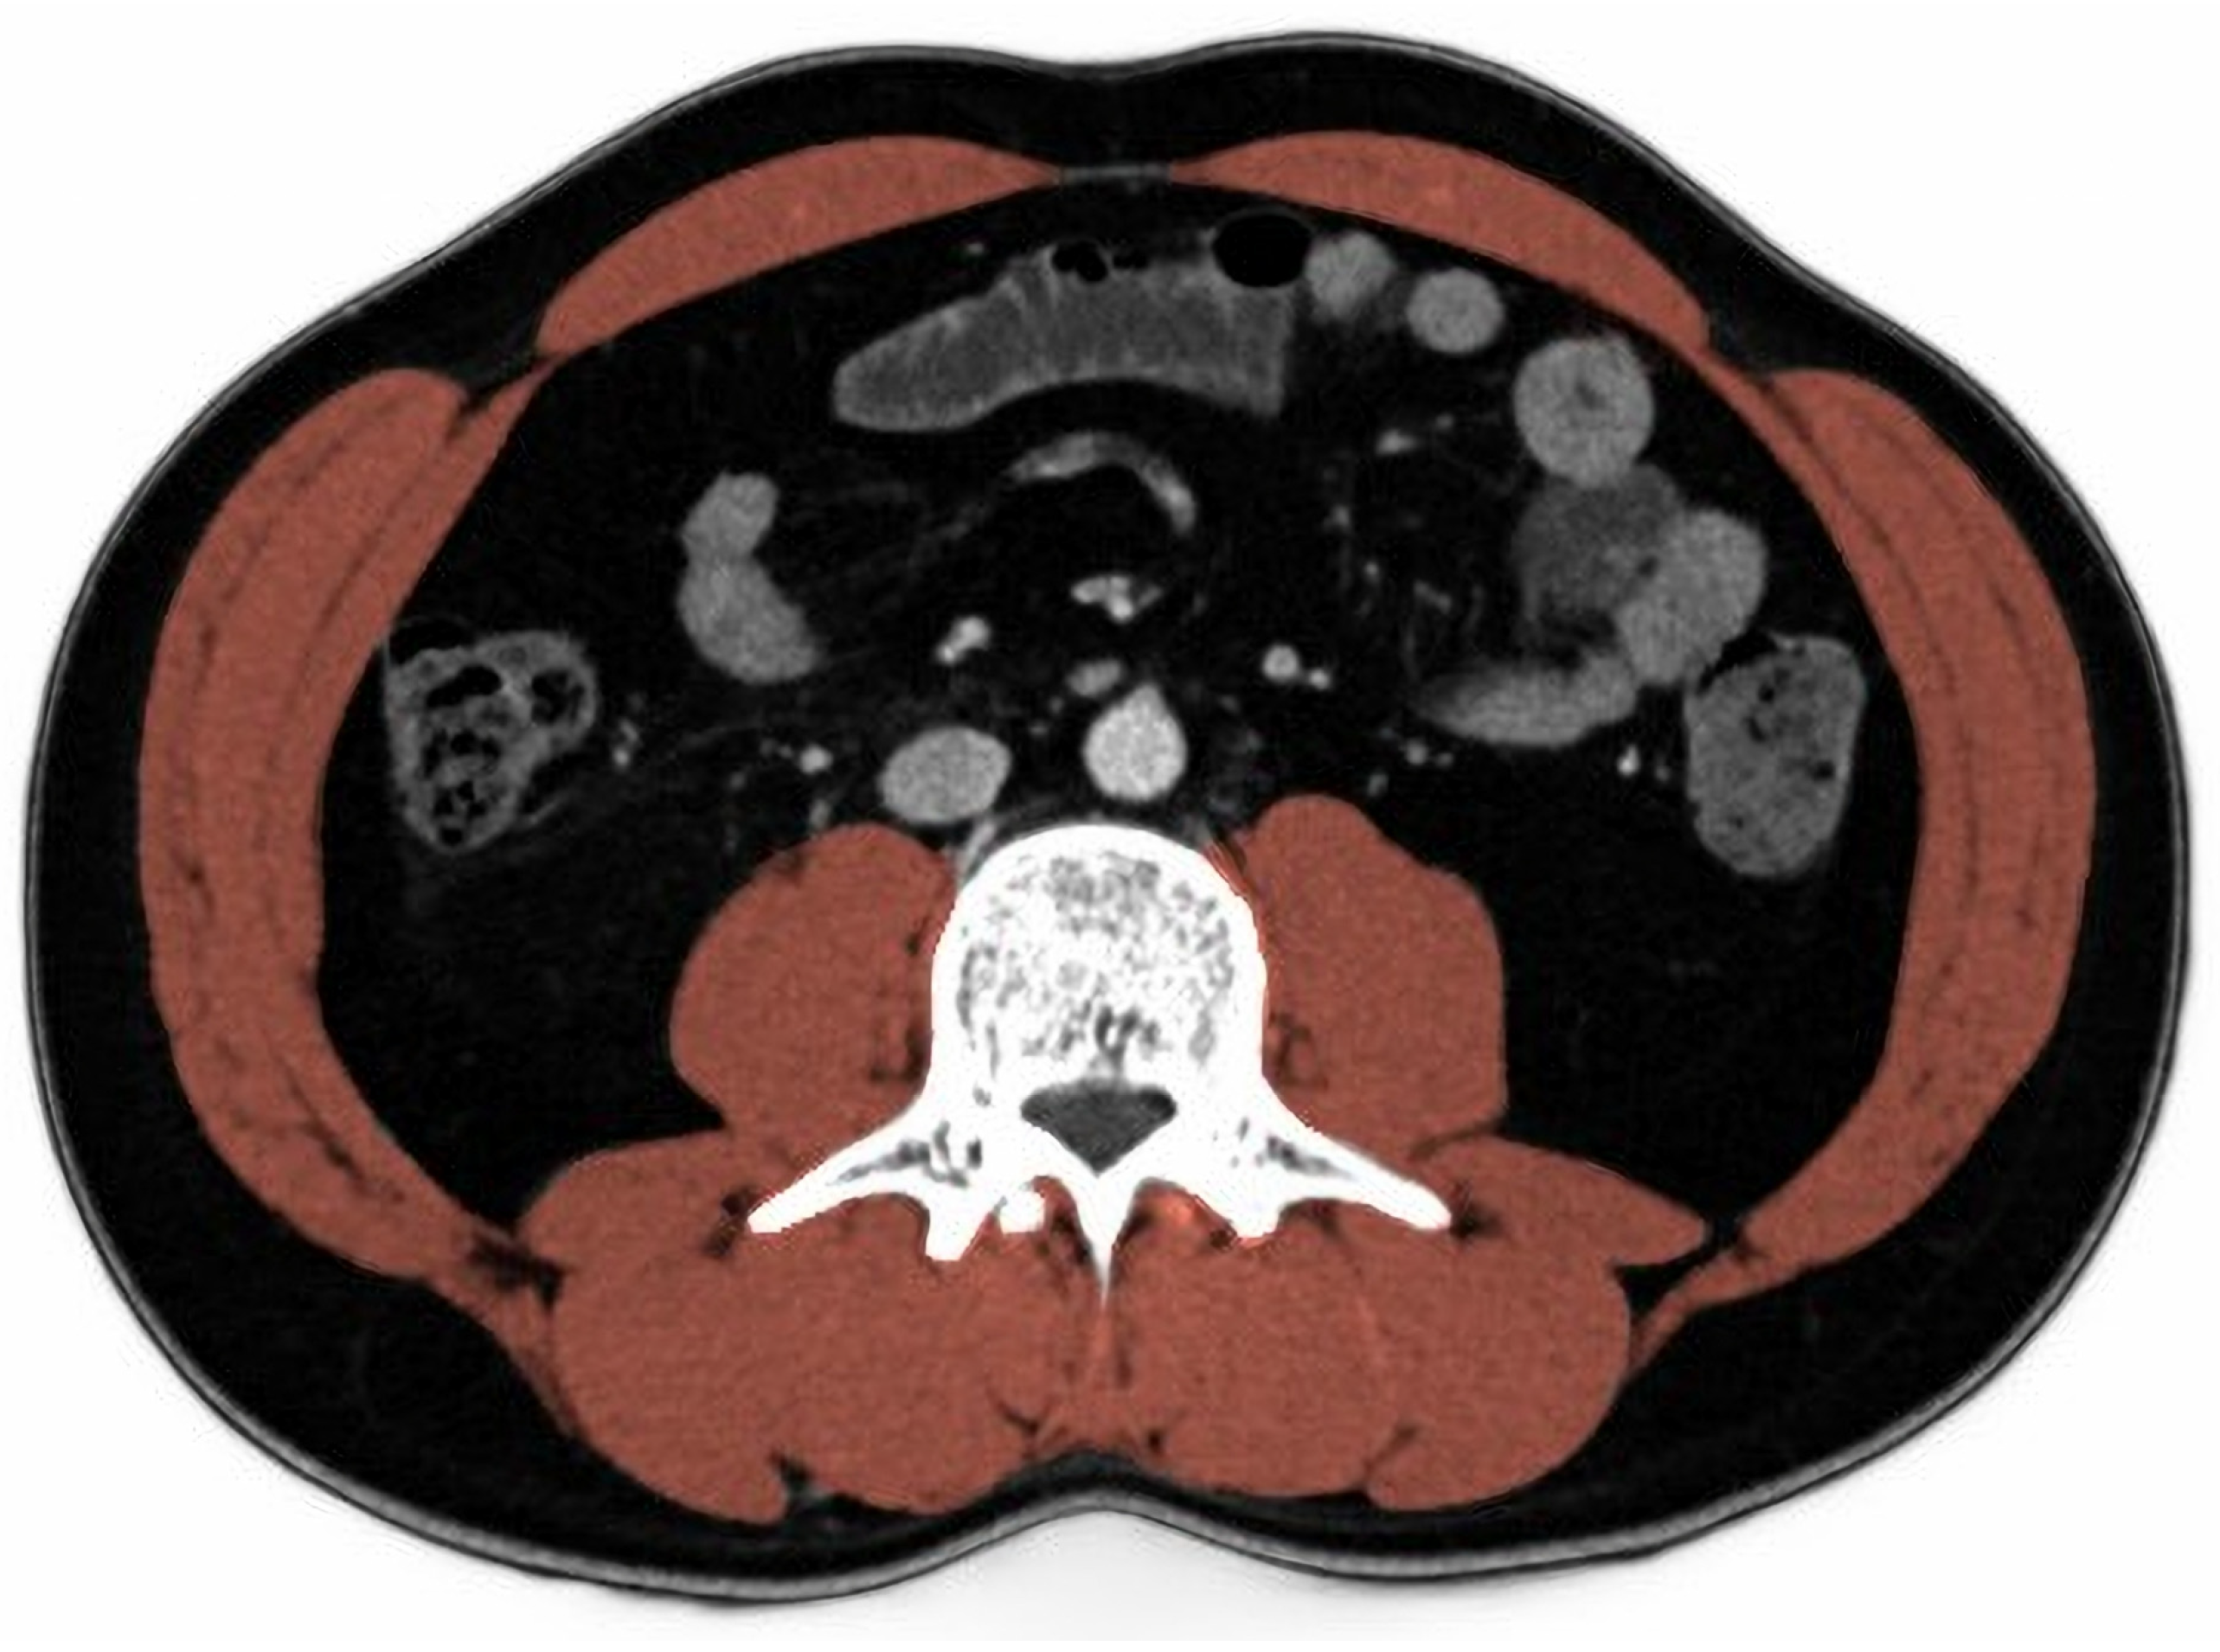

2.4. Skeletal Muscle Index

- Gomez-Perez, S.; McKeever, L.; Sheean, P. Tutorial: A Step-by-Step Guide (Version 2.0) for Measuring Abdominal Circumference and Skeletal Muscle from a Single Cross-Sectional Computed-Tomography Image Using the National Institutes of Health ImageJ. JPEN J. Parenter. Enter. Nutr. 2020, 44, 419–424. [Google Scholar] [CrossRef]

- Gomez-Perez, S.L.; Haus, J.M.; Sheean, P.; Patel, B.; Mar, W.; Chaudhry, V.; McKeever, L.; Braunschweig, C. Measuring Abdominal Circumference and Skeletal Muscle from a Single Cross-Sectional Computed Tomography Image: A Step-by-Step Guide for Clinicians Using National Institutes of Health ImageJ. JPEN J. Parenter. Enter. Nutr. 2016, 40, 308–318. [Google Scholar] [CrossRef] [Green Version]